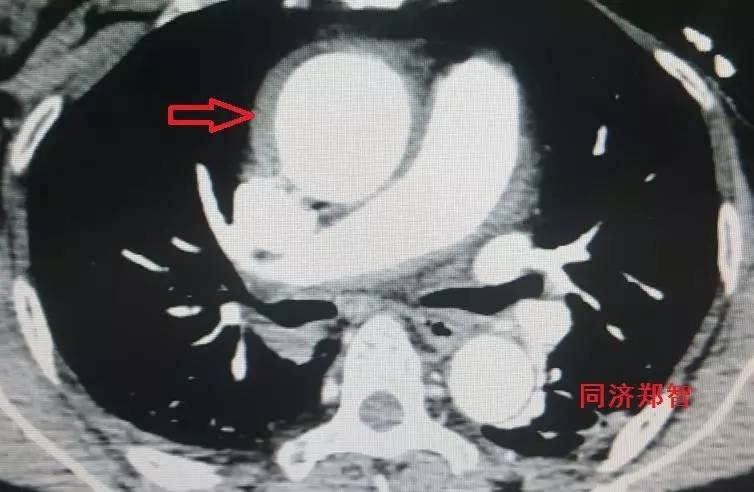

有时候平扫CT也能从血管内密度影的不同来诊断主动脉壁间血肿(图3)。平扫CT提示右肺动脉层面的升主动脉外侧为新月状稍亮的影(红箭头所示)。

图3

CT增强后证实为升主动脉壁间血肿(图4),如红箭头所示。

图4